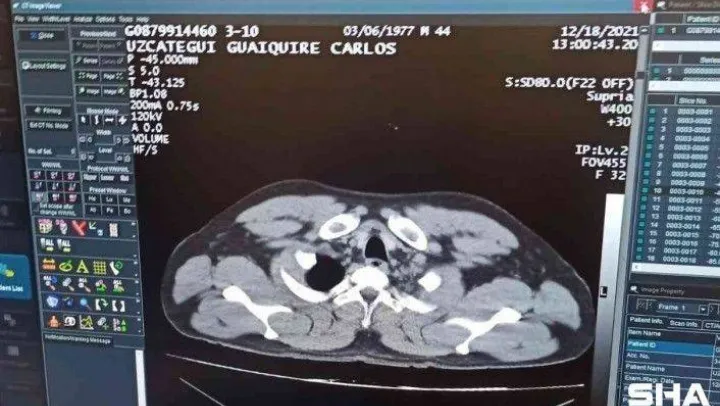

Venuzuella uyruklu C.M.U.G, 18 Aralık 2021 tarihinde Karakas'tan İstanbul'a geldi. Uçaktan indikten sonra pasaport kontrol noktasına doğru ilerleyen şahıs aniden rahatsızlanarak bayıldı. Bunun üzerine olay yerine sağlık ekipleri çağrıldı. Yapılan ilk muayenenin ardından şahıs tedavisi için hastaneye kaldırıldı. C.M.U.G'un hastanede yapılan tomografi kontrolünde mide ve bağırsaklarında 12 adet kapsül tespit kokain tespit edilmesini üzerine şahıs ameliyata alındı. Bağırsakları patlayan uyuşturucu kuryesi tedavi gördüğü hastaneden taburcu edildikten sonra Cumhuriyet Savcılığı'na sevk edildi. Uyuşturucu madde ticareti yapma suçundan mahkemeye sevk edilen kurye tutuklanarak cezaevine gönderildi.